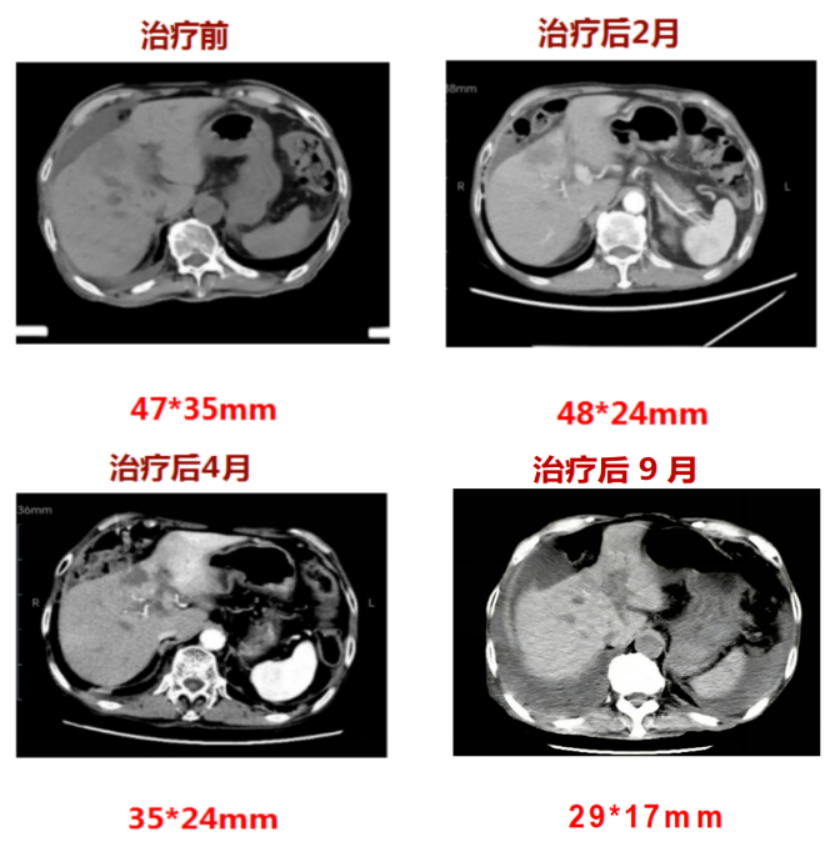

案例二:肝内胆管癌患者

74岁的丘先生,1年前因腹痛就诊于当地医院,行腹部核磁提示肝S4段恶性肿瘤,大小47mmx35mmx37mm,病灶累及胆囊及肝门部胆管,穿刺活检提示中分化腺癌。因患者合并白血病10余年,药物维持治疗期间,不能耐受手术,遂就诊于我院,由乔红梅主任团队开展肝内胆管癌重离子治疗,总剂量68.4Gy(RBE)/18Fx。治疗过程中患者无明显不适反应,后期随访肿瘤逐步缩小,生活质量提升,白血病控制良好。